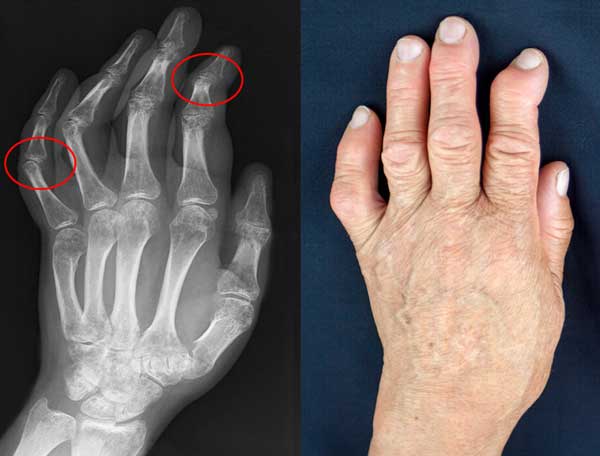

Kerusakan sendi tangan pada hasil rontgen dan kenyataannya

Hasil pengobatan artritis tangan.